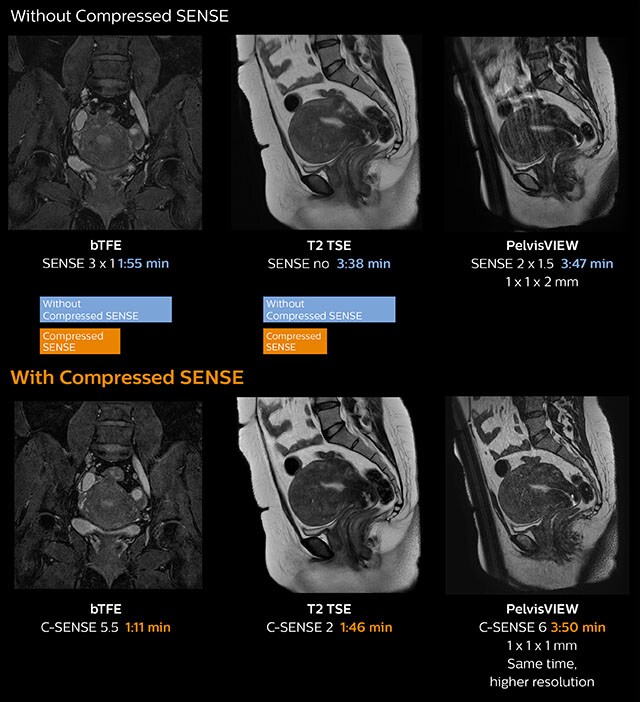

In this MRI exam of pelvis in a patient with myoma, Compressed SENSE is used to accelerate individual sequences and thus the entire examination on Ingenia 1.5T.   Compressed SENSE allowed for a decrease in scan time for the T2 TSE from 3:38 to 1:46 minutes. The Compressed SENSE images in this case show fewer motion artifacts than the images from the previous protocol with SENSE.   In 3D PelvisVIEW, the Compressed SENSE images have a higher and isotropic spatial resolution with a scan time similar to the SENSE sequence. The improved spatial resolution and better contrast in the myometrium of the uterus allowed radiologist Dr. Koyama to confidently diagnose the cancerous lesion in the uterus.   The use of Compressed SENSE accelerates scanning times and increases spatial resolution in 3D PelvisVIEW.